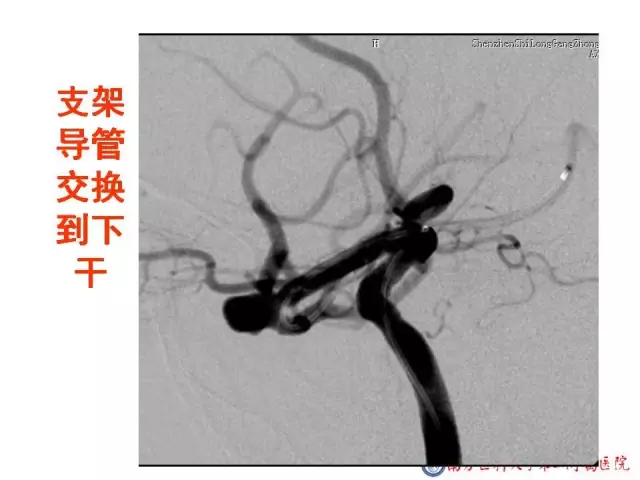

今天为大家分享的是“强生医疗CNV-神经介入专栏”第二十五期,由南方医科大学第三附属医院神经外科主任黄理金教授带来的“Enterprise支架辅助栓塞动脉瘤的优势”精彩讲课视频及PPT,欢迎观看。文章仅代表作者个人观点,如有不同见解,欢迎同道斧正!